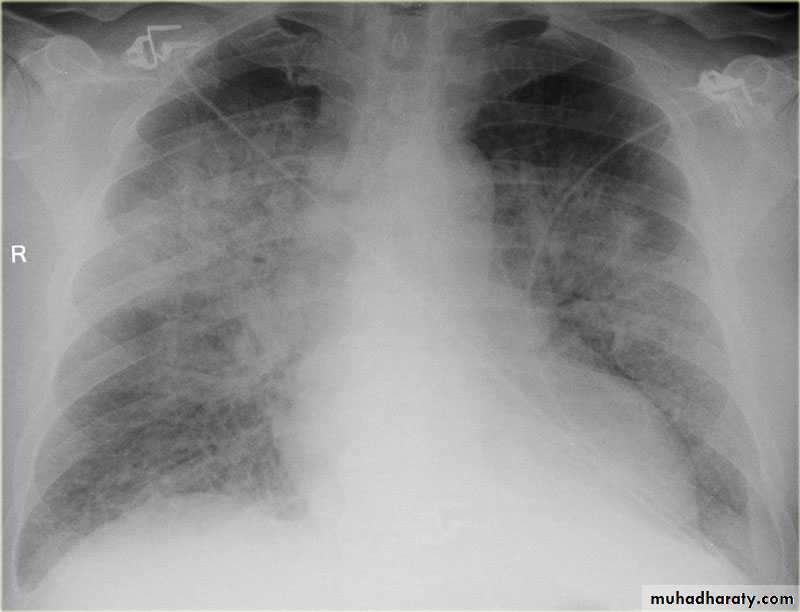

With left sided congestive cardiac failure, the features are that of pulmonary edema which includes:

central pulmonary venous congestion ( prominent hilum )

cephalisation of pulmonary veins ( upper lobe pulmonary venous diversion )

(Septal lines) pulmonary interstitial oedema

pulmonary alveolar oedema

Cardiomegaly

Pleural effusion

Pulmonary edema is a broad descriptive term and is usually defined as an abnormal accumulation of fluid in the extra-vascular compartments of the lung .

radiograph include if pressure > 25 mmHg the findings of :

1.cardiac size/cardio-thoracic ratio: useful for assessing for an underlying cardiogenic cause or association2.Pulmonary Alveolar edema: bat wing pulmonary opacities

3.Pulmonary interstitial edema: presence of peri-bronchial cuffing///septal lines: Kerley lines become more prominent4.pleural effusions

5.Central pulmonary venous engorgement

6.pulmonary blood flow distribution& upper lobe pulmonary venous diversion